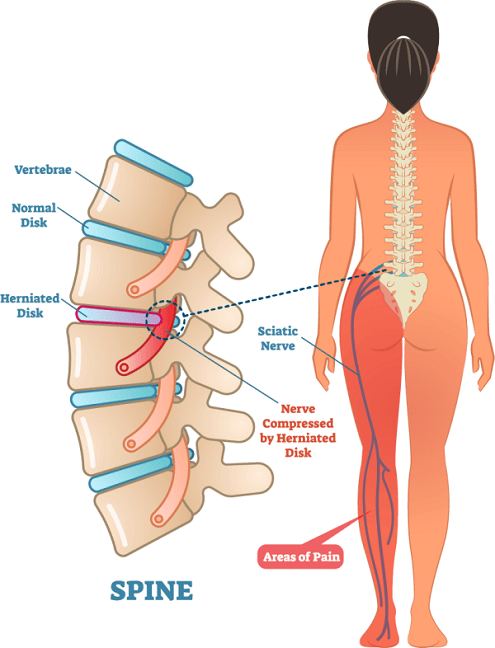

When people say you have a spinal disc bulge, it primarily refers to a bulging out of the disc, or the lava-cake after prolonged periods of time under weight, or through repeated movements in the spine (typically bending forwards). These factors lead to a bulging out of the gooey content of the disc beyond where it would normally be contained. This may lead to other nearby structures getting squished and compressed, resulting in pain which increases in intensity with certain movements (particularly bending forwards), including numbness or pins and needles depending on where the bulge has occurred.